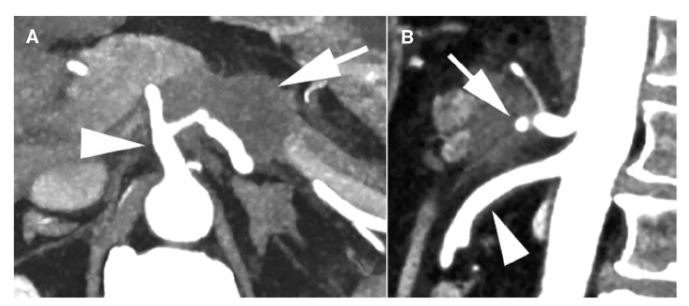

NCCN指南根据局限性PDAC的术前影像学表现的可切除性分为可切除、临界可切除和局部晚期病变(表3)。肿瘤侵犯动脉未超过周径的180度被认为临界可切除,而超过180度通常被认为局部进展(除了下述的例外)(图2)。肿瘤与静脉临近、包绕静脉或血栓形成,但静脉段可重建,均为临界可切除。不可重建的静脉受累认为是局部进展。NCCN指南与其他指南有许多相同建议,除了肿瘤腹主动脉包绕(>180度)的情况例外(表4)。胰体或胰尾肿瘤伴腹腔动脉包绕,但未累及主动脉或胃十二指肠动脉为临界可切除,采用改良Appleby手术(图3)。然而,在其他指南中,存在腹腔动脉包绕被认为是不可切除的。

图3:改良Appleby手术